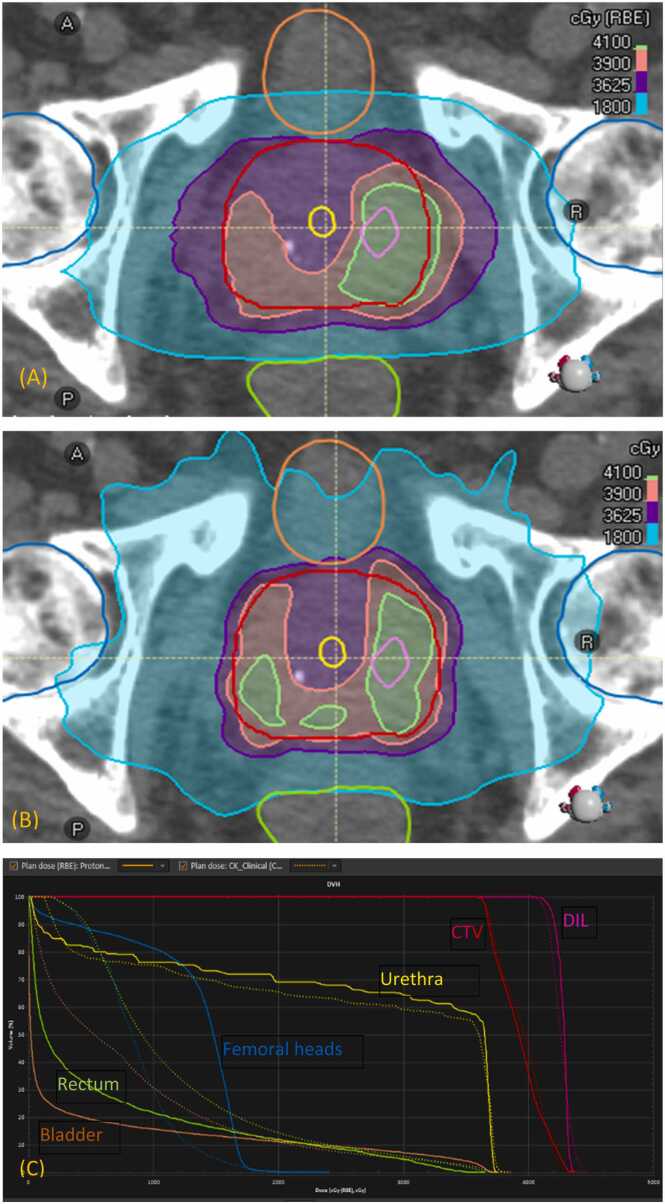

Purpose: To compare intensity-modulated proton therapy with CyberKnife (CK) therapy for hypo-fractionated treatments of prostate with focal boost, as a first planning study for prostate with dose escalation to a dominant intraprostatic lesion (DIL).

Materials and methods: Ten patients who possess one DIL in their prostate and their CK plans that were used to treat the planning target volume of prostate were chosen. Six of the plans were further escalated to DIL. Intensity-modulated proton therapy plans were created for the patients with robust optimization, accounting for setup and range uncertainties for the clinical target volume (CTV) of prostate. The CK plans were then compared with the proton plans.

Results: In the worst scenario of the robust evaluation, the proton plans reasonably met all objectives and constraints used in CK planning for both CTV coverage and organs-at-risk (OAR) sparing. Under the nominal scenario of the robust optimization, the proton plans produced dosimetric values comparable to those by the CK plans for both CTV and DIL coverage. The average dose to CTV, outside DIL and urethra, was found lower in the proton plans than in the CK plans due to the uncertainties. A similar trend was observed for the dose conformity to CTV. These two findings, however, were not planning objectives. Regarding organs-at-risk sparing, the proton plans in the nominal scenario were comparable to the CK plans for doses >18.125 Gy; for doses below it, the proton performed better. This study offers a basis for a clinical trial of treatment of prostate cancer by proton that may be transferred from the CK system in our center.

Conclusion: The dosimetric objectives and constraints used in the CK plans were achieved with the proton plans.